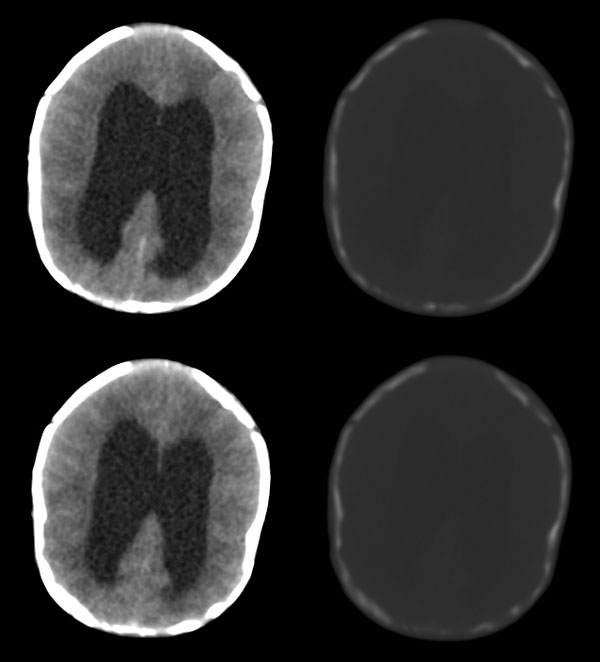

枕骨缺损,脑膜脑膨出。同时第4脑室挤压变形、闭塞,致使第3脑室、双侧侧脑室显著积水、扩张,过高的颅内压推挤脑实质,致使颅骨内板出现多而且深的脑回样压迹,脑细胞水肿,皮质、白质分界不清。

颅骨内面凹陷——过高的颅内压推挤脑实质,过高的颅内压推挤脑实质,致使颅骨内板出现多而且深的脑回样压迹

从图像分析看到的是三、侧脑室的积水,颅骨凹凸不平应是脑压高引起的,脑膜膨出是因脑压增大所致。综合考虑是:中脑水管发育畸形(狭窄或闭锁不全)并三、四脑室积水。枕骨发育不全伴脑脊膜膨出。

脑膜膨出没有问题,但是颅骨怎么长成这样,还是第一次看到;